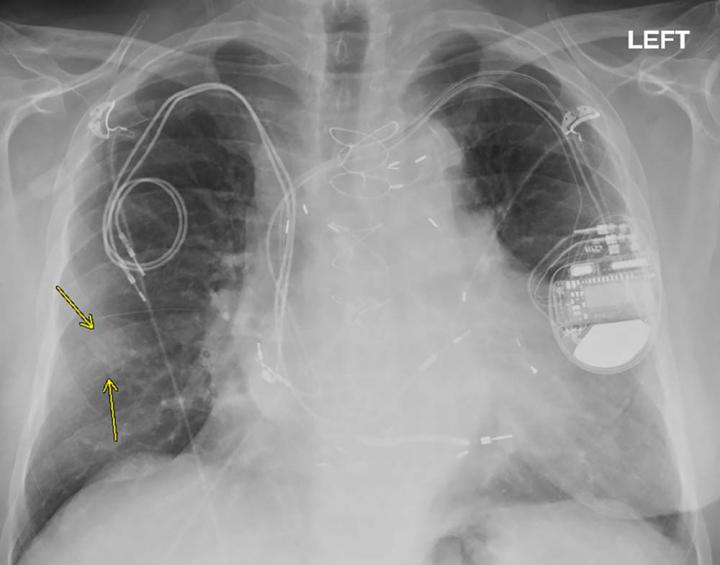

Millions of people around the world rely on implanted cardiac devices like pacemakers and implantable cardioverter defibrillators (ICDs) to help control abnormal heart rhythms. MRIs are discouraged or prohibited in many of these people over fears that the powerful magnet of the scanner will heat the metal in the devices, potentially damaging heart tissue and harming the devices.

Prior research has demonstrated the safety of performing MRI exams in patients with non-MR conditional devices. However, those studies did not account for pacemaker-dependent ICD patients, or patients whose hearts won't function if the defibrillator is removed or stops working. Other groups not accounted for in previous studies include patients undergoing chest and cardiac MRI exams and patients with abandoned or fractured leads, or wires that connect the device to the heart.

Patients had their devices checked before and after each MRI and had their vital signs monitored closely by a nurse during their time in the scanner. Devices were turned to asynchronous mode in pacemaker-dependent patients before they went in the scanner. ICD patients had tachycardia therapies disabled during the MRI.

The results demonstrated that MRI exams--including chest MRI exams--can be performed safely in pacemaker-dependent ICD patients and in patients with non-MR conditional devices or abandoned leads.